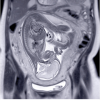

This course provides a clinical perspective of PET/CT imaging and the emerging use of Theranostic agents within Nuclear

Medicine. A broad perspective on the economic, clinical, and academic aspects of the latest trends in PET/CT imaging

and Nuclear Medicine therapy will be presented.

• Describe new developments in the merger of diagnostic and therapeutic radioligands for PET/CT imaging

and therapy with specific focus on DOTA, PSMA, and PRRT

• Identify the key clinical indications for new emerging tracers for Neuroendocrine Tumor and Prostate cancer

using somatostatin receptor and PSMA PET/CT imaging